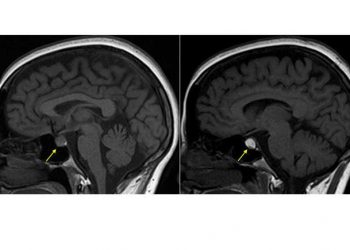

Apopleksi, beyin damarlarından birinde ani yırtılma sonucu veya tıkanma sonucu gelişen bilinç kaybı ve felç oluşumuyla belirgin tabloya denir. Apoplexy